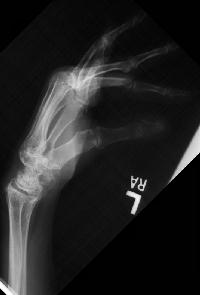

Clinical Example: Rheumatoid arthritis with DRUJ and radiocarpal involvement

Rheumatoid arthritis has many forms of presentation. This patient has bilateral severe radiocarpal and distal radioulnar joint involvement, with relative sparing of the metacarpophalangeal and interphalangeal joints.

Note the spontaneous radiolunate fusion.